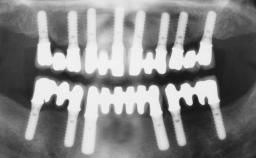

The staged approach permits the transition from an “irrational to treat”dentition to a full arch implant supported restoration without any need to use a removable provisional prosthesis or to apply the immediate-placement and immediate-loading techniques. A failing dentition is the usual indication for a staged treatment. On the other hand, the dentition should still contain many residual teeth, but with few or none of them being suitable for use as definitive abutments for a full-arch fixed restoration.This situation is usually the result of advanced periodontal disease or of the failure of an extensive fixed prosthesis.